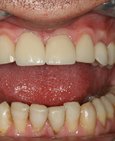

Výchozí stav – nevyhovující tvar, barva a kazivá destrukce a vpravo estetická rekonstrukce churpu pomocí keramických korunek

Estetická rekonstrukce chrupu pomocí keramických korunek